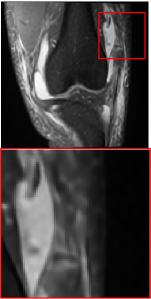

Figure 5 provides the qualitative comparison of the various methods on the four datasets at a scale of 4. The top, second, third, and bottom rows are the SR results under the FastMRI, clinical brain, clinical tumor and clinical pelvic datasets, respectively. The red boxes indicate the zoom-in region of complicated anatomical structures along with their corresponding error maps. Note that the brighter textures in the error maps, the lower the quality of the reconstructed images. As can be seen, compared to methods based on Transformers and CNNs, diffusion-based methods like DisC-Diff and DiffMSR (Ours) are capable of reconstructing high-realistic images with promising reconstruction metric scores (PSNR and SSIM). Nevertheless, while DisC-Diff can reconstruct high-precision MR images, it does not preserve the structure present in the original HR images, introducing some additional information that can affect medical diagnosis. In contrast, our method combines DM and PLWformer, which can preserve the original image’s structure while restoring high-frequency information.

In this section, we present more visual qualitative comparisons. Figures 8, 9, 10, and 11 show the reconstruction results of each method in FastMRI, clinical brain, clinical tumor, and clinical pelvic, respectively. As can be seen, although DisC-Diff can reconstruct MR images with high-frequency information, it fails to preserve the structure and content of the original Target HR image effectively, resulting in image distortion. In contrast, our proposed DiffMSR can restore high-frequency information while preserving the structure of the original HR image, indicating the effectiveness of the joint use of DM and PLWformer.